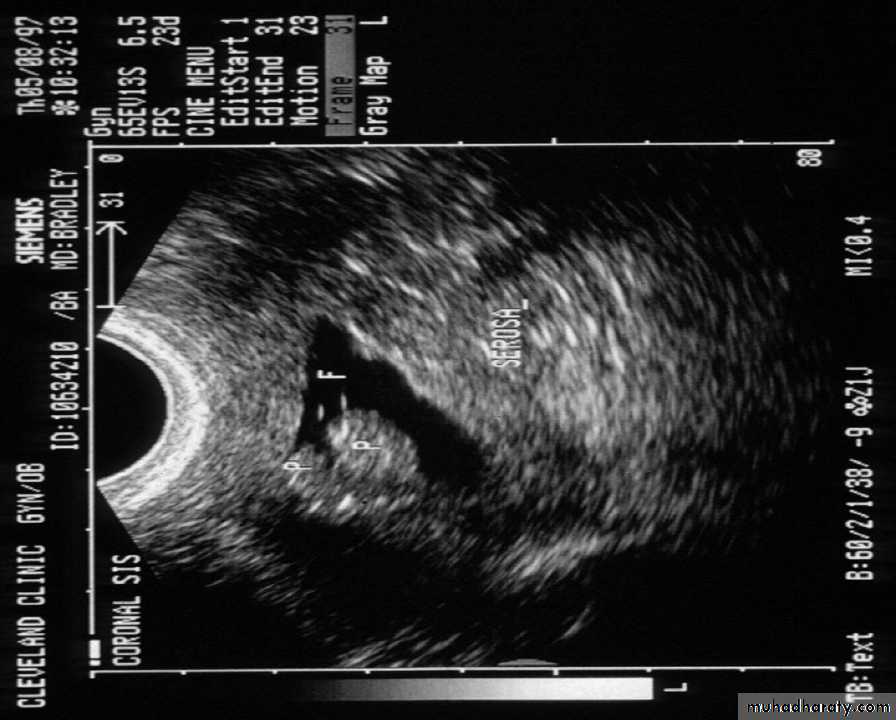

A refinement of vaginal probe ultrasound is saline infusion sonography (SIS). A salt water (saline) solution is injected into the uterus with a small tube (catheter) before the vaginal probe is inserted. The presence of liquid in the uterus helps make any structural abnormalities more distinct. These two non-invasive procedures cause less discomfort than endometrial biopsies and D & Cs, but D & C still remains the definitive test for diagnosing uterine cancer.

if the endometrial thickness is >5mm. and if the patient pre test probability is low ,office endometrial biopsy and SIS should be done to determine whether the endometrium is symmetrically thickened.